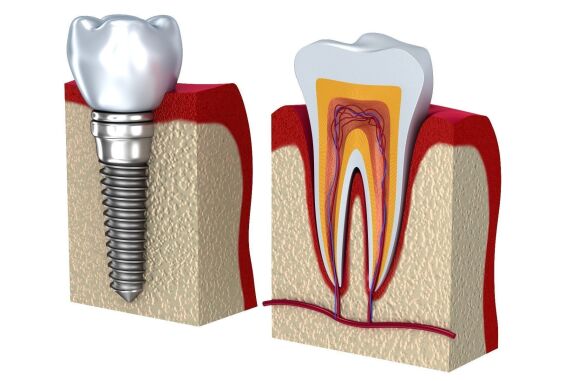

قبل از هرچیز بهتر است به طور مختصر به تعریف خود ایمپلنت بپردازیم. ایمپلنت در لغت به معنی کاشت است. در دندان پزشکی از روش ایمپلنت یا کاشت دندان برای پر کردن جای خالی دندانهای از دست رفته استفاده میشود. گاهی اوقات ممکن است دندانها بر اثر ضربه شدید، پوسیدگیهای عمیق، بیماریهای لثهای، عفونت و... از بین بروند. در چنین مواردی کاشت دندان یا ایمپلنت بهترین روش برای جایگزین کردن این دندانهاست. زیرا پایه ایمپلنت که در استخوان و لثه قرار میگیرد از جنس تیتانیوم بوده که کاملاً با بدن سازگار است و با مقاومت بسیار بالایی که دارد میتواند وظیفه ریشه دندان را به عهده بگیرد.

درمان ایمپلنت به شما این اجازه را میدهد که پس از تکمیل دوره درمان، دندانی طبیعی داشته باشید و بدون نگرانی مثل سابق به خوردن و جویدن ادامه دهید. این روش نسبت به روشهای قدیمی مانند بریج هم میزان موفقیت بیشتر و هم عوارض کمتری برای لثهها و دندانهای مجاور دارد.

انجام ایمپلنت یکی از حساسترین درمانهای پزشکی است، زیرا در این روش قرار است جسمی خارجی وارد استخوان فک و لثه شود. هرچند پایه ایمپلنت با جنس تیتانیوم بیشترین سازگاری را با بدن انسان دارد، اما در طول دوره درمان نیاز است نکاتی را رعایت کنید تا از بروز مشکل در هنگام جوش خوردن استخوان با فیکسچر جلوگیری شود.